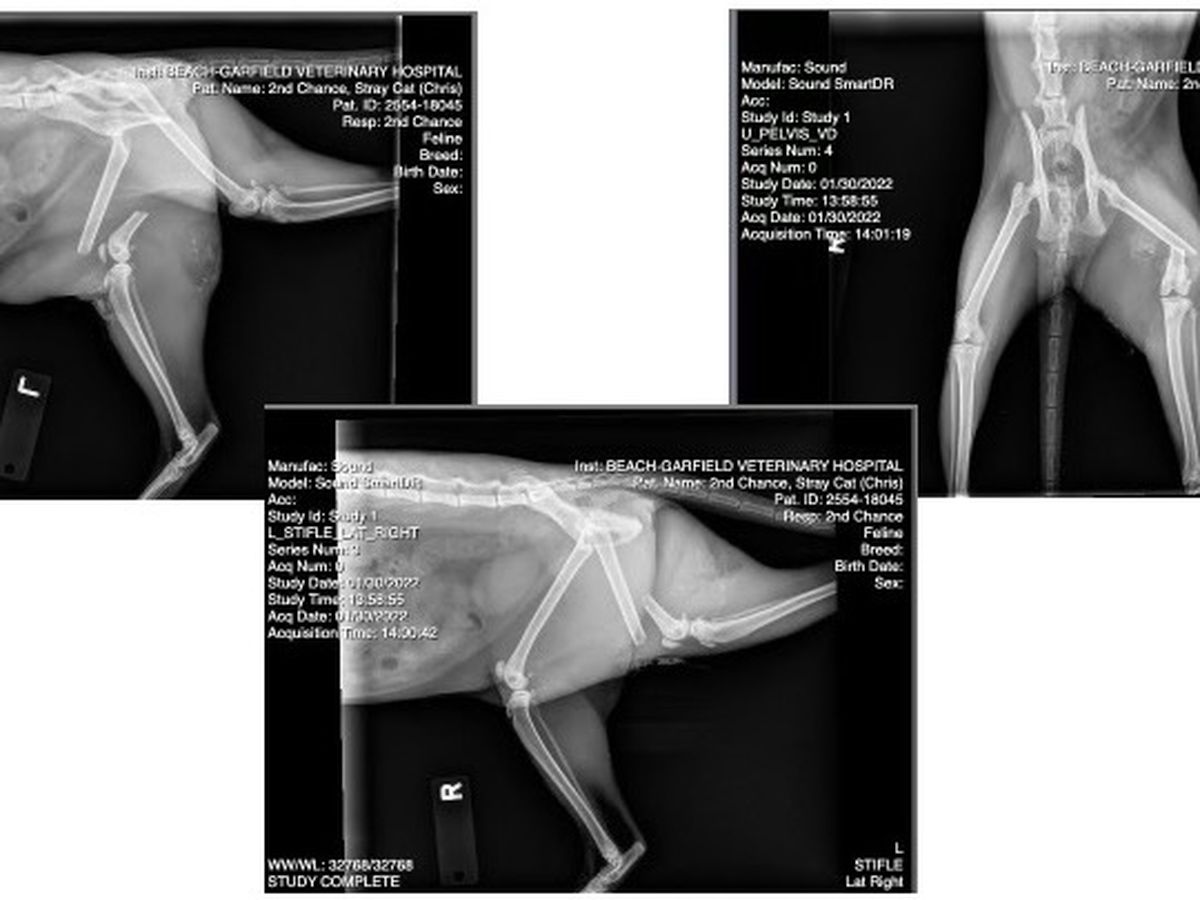

Second Chance Pet Adoptions received a call about a one year old injured cat named Chris who was most likely hit by a car. She was taken to Beach-Garfield Veterinary Hospital where they discovered she had a broken leg and urgently needed surgery which resulted in mounting hospital bills. Please help us with donations. No amount is too small. Thank you!